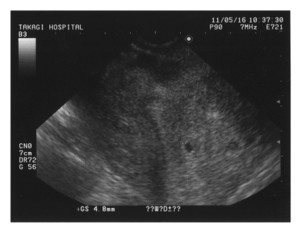

突然ですが、今年の1月初め、我が家の愛犬がお亡くなりになりました。享年2.5歳。ペギニーズとシーズーのMIX。昨年末に歯石を取りに獣医さんに行ったら、麻酔の関係で血液検査。結果は生きているのが不思議なくらいの数値。腎臓の機能がほとんど無い状態。歯石どころではなく、即、治療開始。